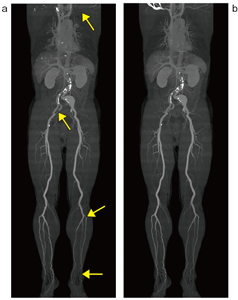

一方、ziostation2の体幹部骨除去の処理精度においては、「高精度処理」は「高速処理」と比べて、より細かいサンプリングと、より多くの近傍のマトリクス計算を行う。そのため「高精度処理」は、物体の値の連続性を判別することが可能であり、精度の高い骨除去が行われる。体幹部骨除去の処理精度について、処理時間計測と同様の症例にて「高精度処理」と「高速処理」を、excellent、good、fair、poorの4段階で評価した結果を示す(図2)。ziostation2では、「高精度処理」を使用した体幹部骨除去の精度が飛躍的に向上しており、従来難しかった骨と血管が近接した部位でも抽出が可能となっている。「高速処理」では下腿部分の骨と動脈の分離が正確に行えず血管が欠ける場合があるが、「高精度処理」では、多くの場合は改善する傾向が見られるため、細かい末梢血管が必要な場合には「高精度処理」を使用し、大血管の抽出のみで十分な場合には「高速処理」使用するなど、目的や症例によって使い分けることが可能である(図3)。体幹部骨除去処理において、「高精度処理」は「高速処理」に比べて処理時間を要するが、精度の高い骨除去処理により手動での修正等にかける時間も短縮できるため、結果的には効率的な処理が可能である。この「高精度処理」の骨除去実行後は、「骨除去記憶ファイル」が自動作成され、その後、連続作業時に「高精度処理」実行すると約1秒程度でスピーディに骨除去の画像処理を得ることができる。

![]() 図3 体幹部骨除去処理における高速処理(a)と高精度処理(b)の3D- CTA画像 高速処理は、高精度処理と比べると骨と血管が近接した部位において末梢血管の描出に劣っていることがわかる。 |